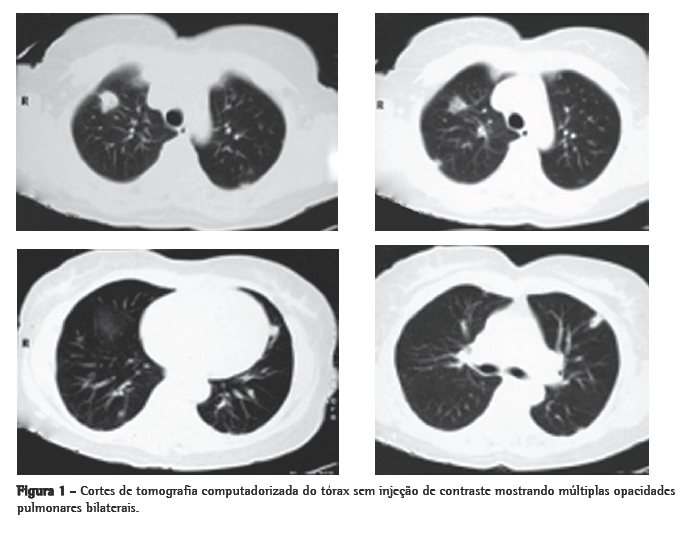

A tomografia computadorizada de tórax de controle após este curso de antibióticos mostrou regressão praticamente total das opacidades (Figura 2). Permaneceu afebril desde o terceiro dia do novo curso de antibióticos. Nenhum microrganismo foi isolado das hemoculturas e culturas do lavado broncoalveolar. A anticoagulação foi suspensa após 20 dias de uso, pela falta de evidência de benefício na síndrome de Lemierre.